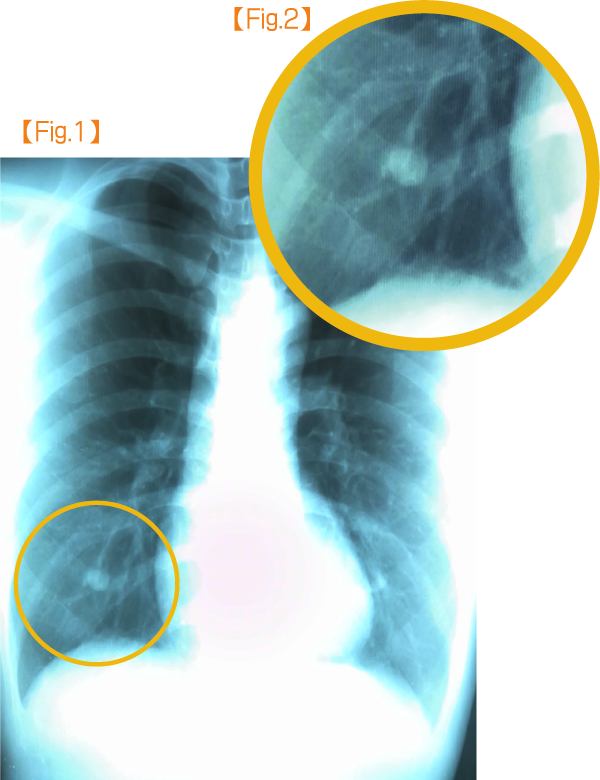

女性の場合は乳頭の影が肺に重なって写ってしまうことは珍しくなく、肺がんなどの病変と見分けがつかない場合もしばしばです。

当院では、乳頭の可能性が高い影があった場合【Fig.1(病変拡大Fig.2)】には、乳頭部にご自身で金属クリップを張り付けていただいて再撮影【Fig.3(病変拡大Fig.4)】して、2枚のフィルムを比較して、影が乳頭に一致することを確認しています。